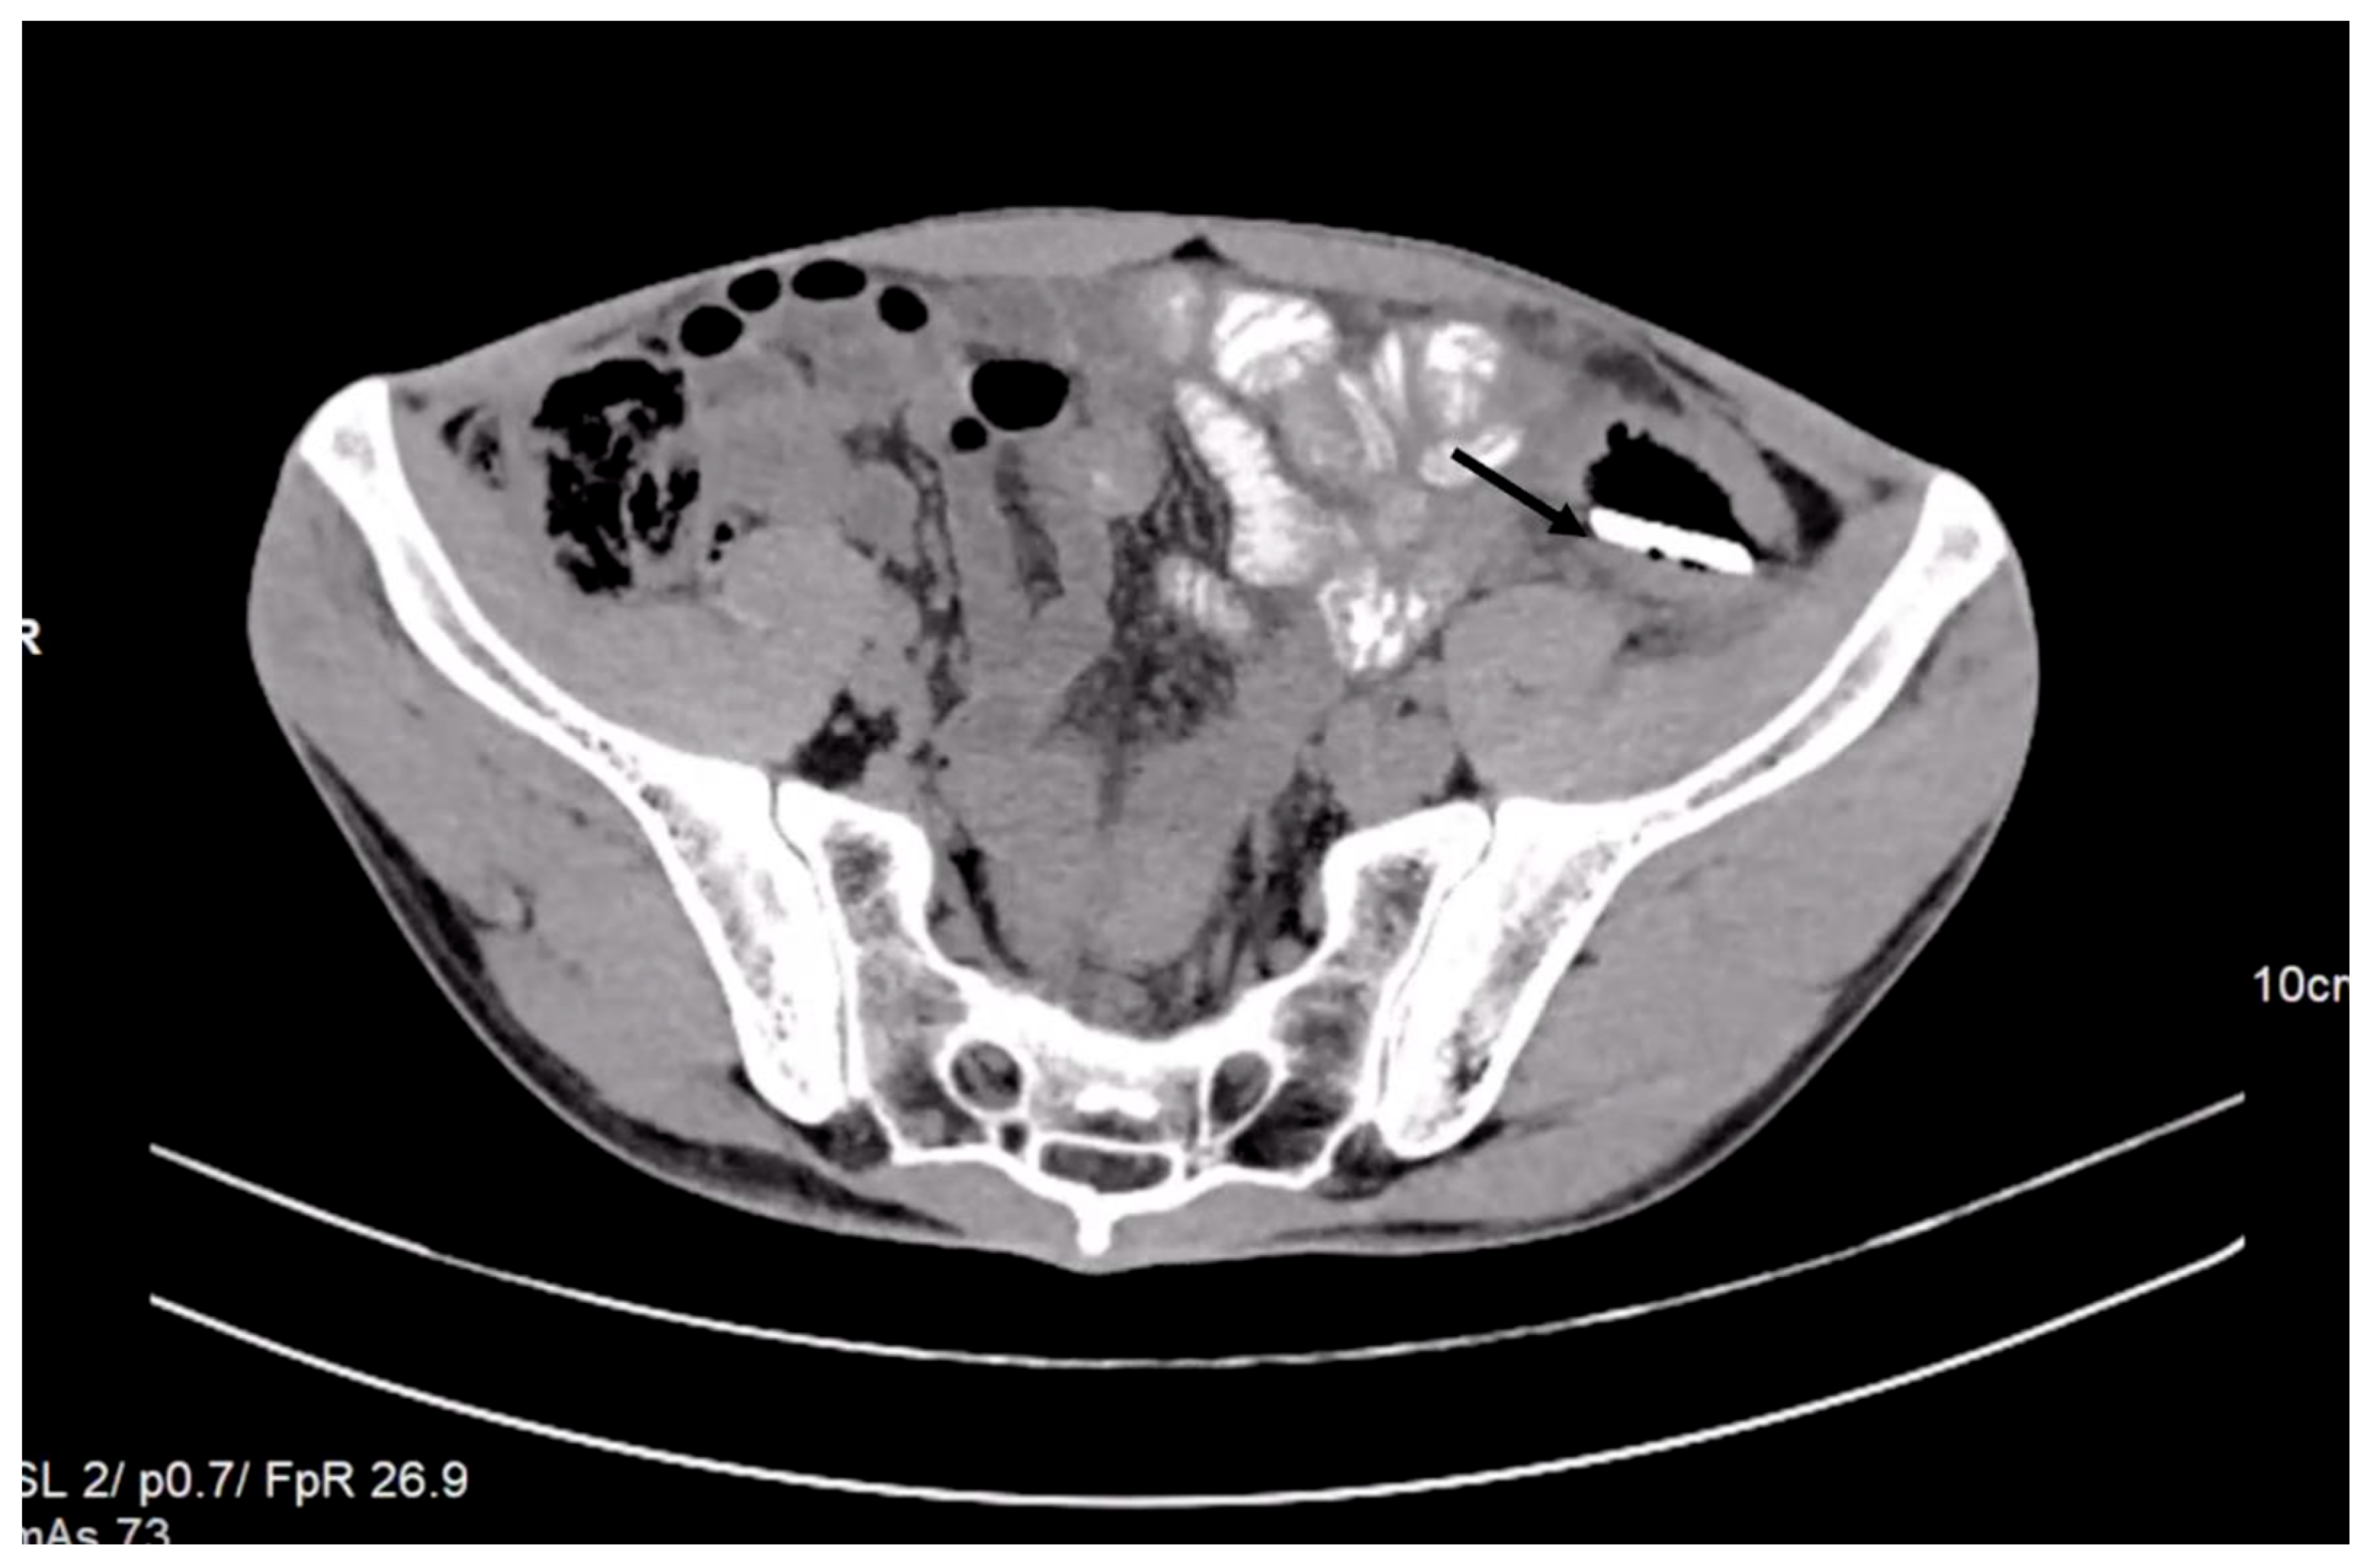

The laboratory examinations of the patient showed leukocytes = 9830/μL, hemoglobin = 12.8 g/dL, platelets = 379,000/μL, ALT = 69 U/L, AST = 48 U/L, PT = 13.6 s, and the rest within normal limits. A chest X-ray at admission showed no acute pleuro-pulmonary lesions. An abdominal X-ray at admission showed discrete aerocolia without radiologically noticeable pneumoperitoneum, hydroaeric levels, and a radiopaque structure in the left flank, denoting a foreign body (Figure 1).

Figure 1. X-ray examination showed an elongated blade (arrow) in the iliac fossa, possibly in the sigmoid colon.